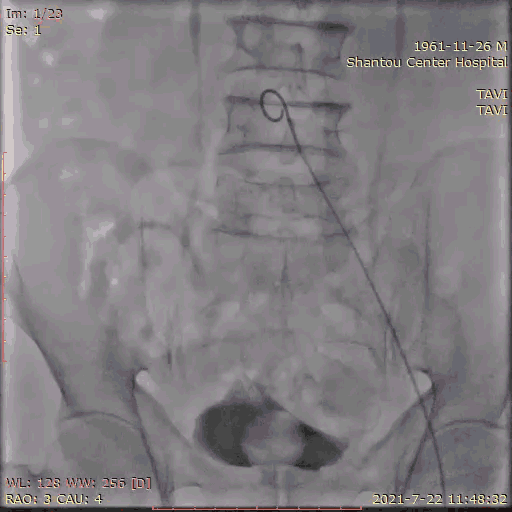

主动脉根部造影

临时起搏器植入后,辅入路穿刺,猪尾导管置于无冠窦底进行主动脉根部造影。

初步判断释放体位是否合适。

观察瓣叶活动度、是否合并反流,有利于跨瓣。

左右冠通畅,存在一定反流,有一定耐受能力,球扩时,循环崩溃风险较小。

左冠窦瓣叶活动度高、无钙化,无冠窦右冠窦活动度减轻,且钙化集中在基底部,右冠风险较左冠低。